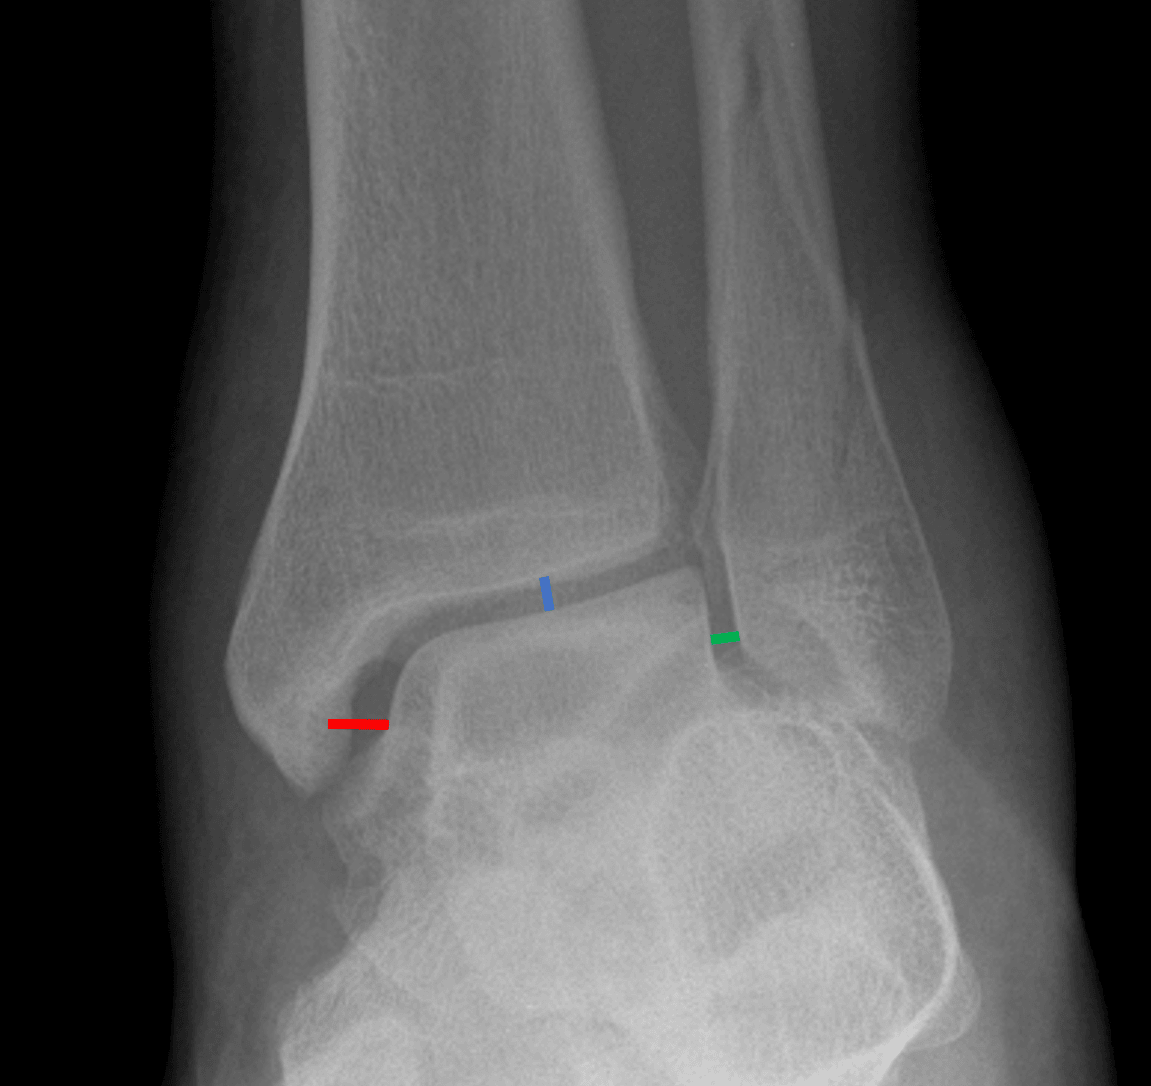

Medial clear space widening. The medial clear space (red line) should not be wider than the other aspects of the ankle mortise (blue and green lines).

Slight widening of the medial clear space raises concern for deltoid ligament injury.

• Weber type B: lateral malleolar fracture with fracture line exiting medially at the level of the talar dome – these are stable if the medial structures are intact: look for widening of the medial clear space (indicating deltoid ligament injury) and widening of the distal tibiofibular syndesmosis